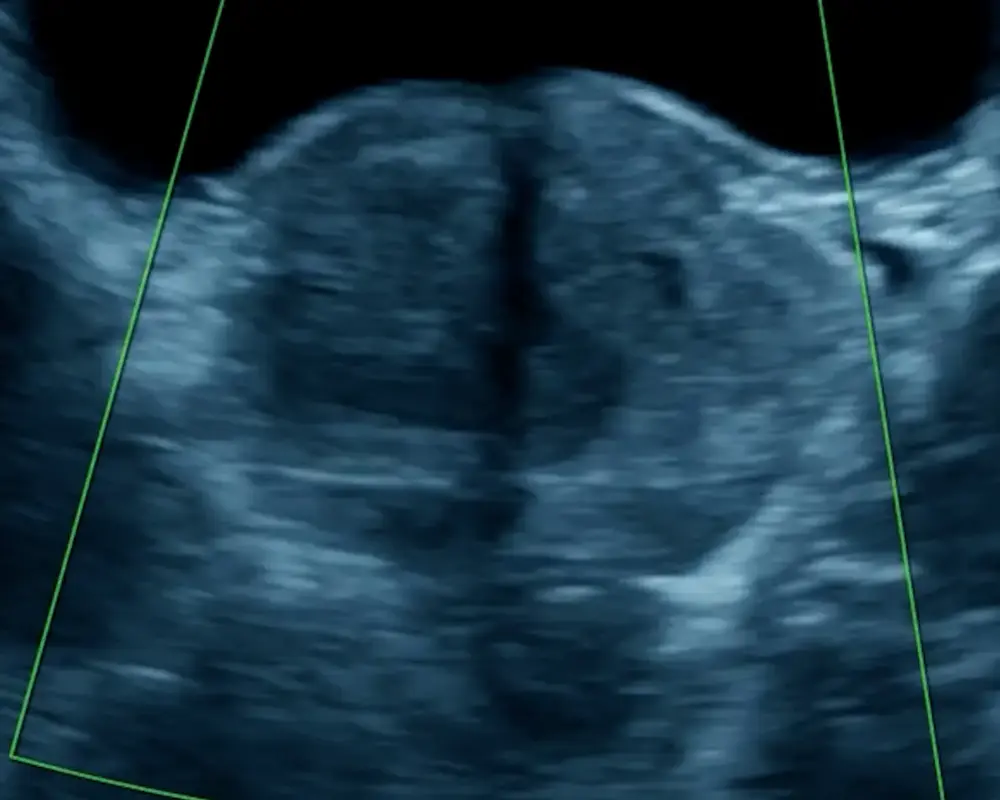

Pelvic Ultrasound

Pelvic ultrasound imaging helps assess reproductive organs, bladder conditions, and internal concerns, supporting accurate diagnosis and treatment planning with clear imaging results.